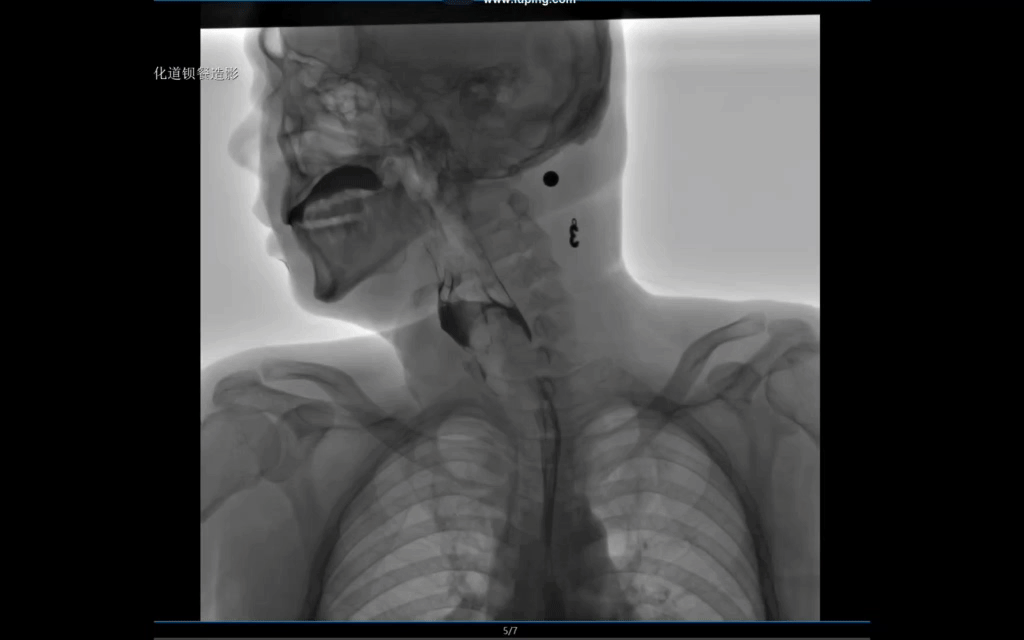

采用新一代動(dòng)態(tài)平板探測(cè)器,兼具動(dòng)靜態(tài)采集功能,輕松實(shí)現(xiàn)數(shù)字?jǐn)z影、數(shù)字胃腸、數(shù)字透視、數(shù)字造影、實(shí)時(shí)高清點(diǎn)片、視頻保存和回放等功能,滿足多科室臨床檢查需求。

對(duì)稱設(shè)計(jì)床體,配合球管大角度擺臂,可實(shí)現(xiàn)無(wú)死角擺位;床體起倒自如、移動(dòng)自如,應(yīng)用廣泛;SID可電動(dòng)拉伸至1.8米,滿足標(biāo)準(zhǔn)胸片和塵肺病鑒定檢查需求;電動(dòng)控制的360°無(wú)限位旋轉(zhuǎn)腳踏板設(shè)計(jì),使病人無(wú)需轉(zhuǎn)動(dòng),即可快速、高效完成多角度的觀察?;谂R床需求的多種智能化設(shè)計(jì),讓設(shè)備操作更加方便快捷。

大熱容量雙焦點(diǎn)高速球管,輕松應(yīng)對(duì)高強(qiáng)度臨床工作;超大功率、高頻逆變式高壓發(fā)生器,源頭上保障整機(jī)品質(zhì);標(biāo)配雙高密濾線柵,專距專用,進(jìn)一步提升圖像品質(zhì),同時(shí)采用先進(jìn)脈沖透視技術(shù),實(shí)現(xiàn)低劑量和高清圖像完美融合,既能為臨床提供精準(zhǔn)診斷依據(jù),也能為兒童及需要多次攝片的患者提供進(jìn)一步的呵護(hù)。